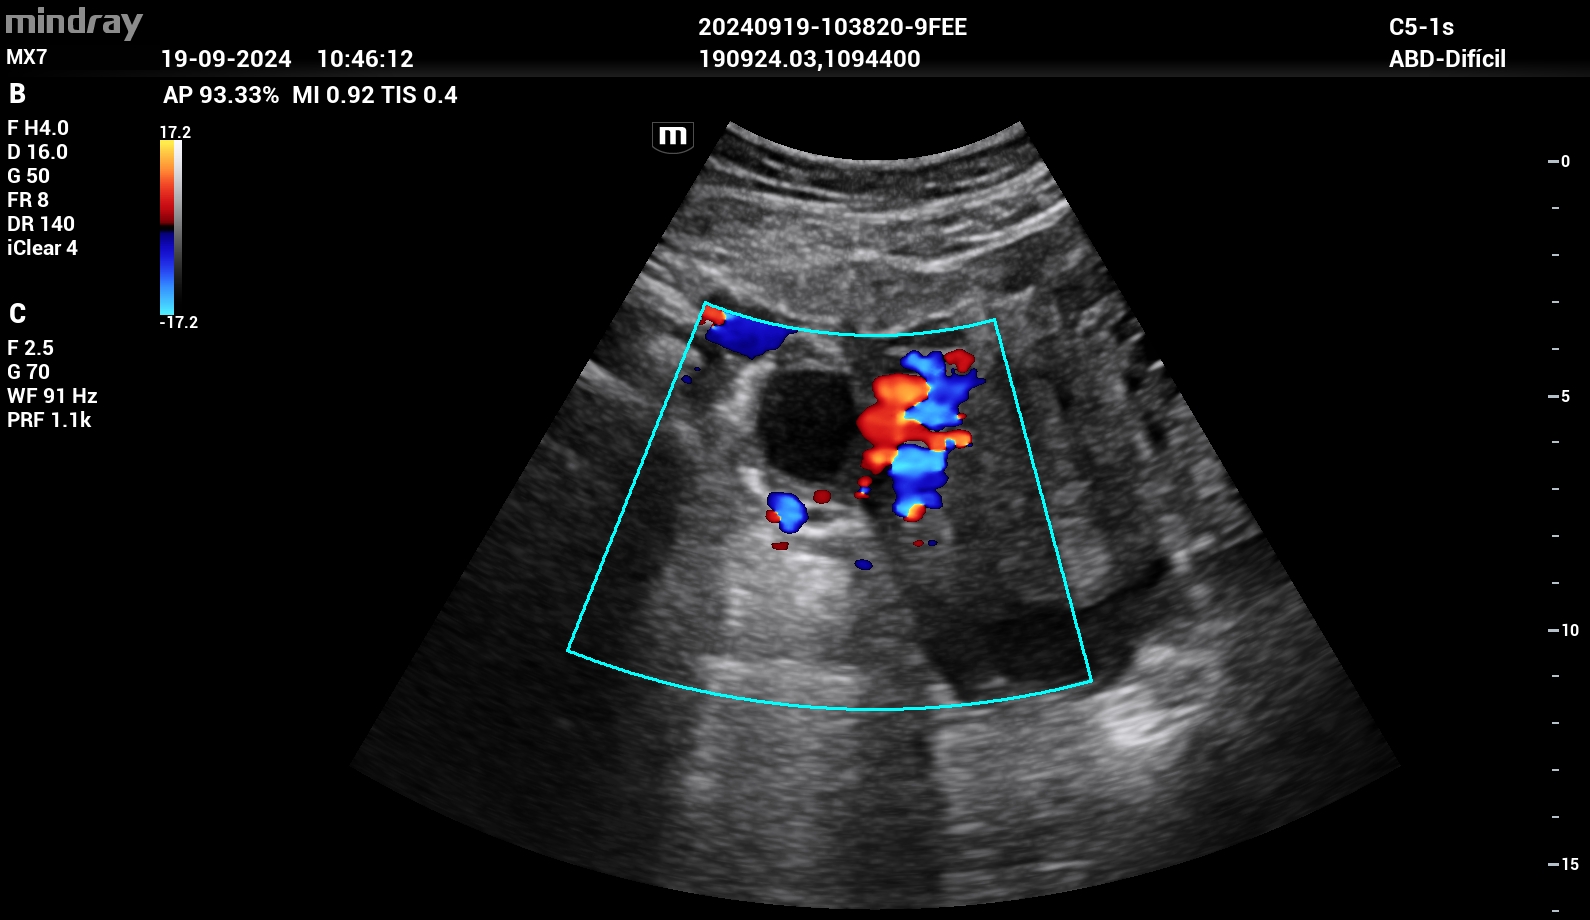

Se realizó ecografía clínica donde se objetivó líquido libre intraabdominal en espacio de Douglas. Útero en anteversión sin vesícula gestacional en interior. En región paraovárica derecha presentaba imagen ecomixta de 40 x 31 mm sugestiva de embarazo ectópico.